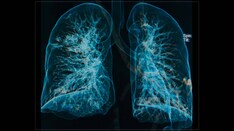

We're going to talk about COPD in older adults. We had two great guests on this podcast. We learned that as people get older, their lungs get older as well. And on balance, that means the thoracic cage has some changes. There is less elastic recoil and the respiratory muscles don't work as well. In most people that ends up looking like a more obstructive pattern if you were to get spirometry. But Paul, does that mean that we can diagnose every older adult with COPD just because they have abnormal spirometry?